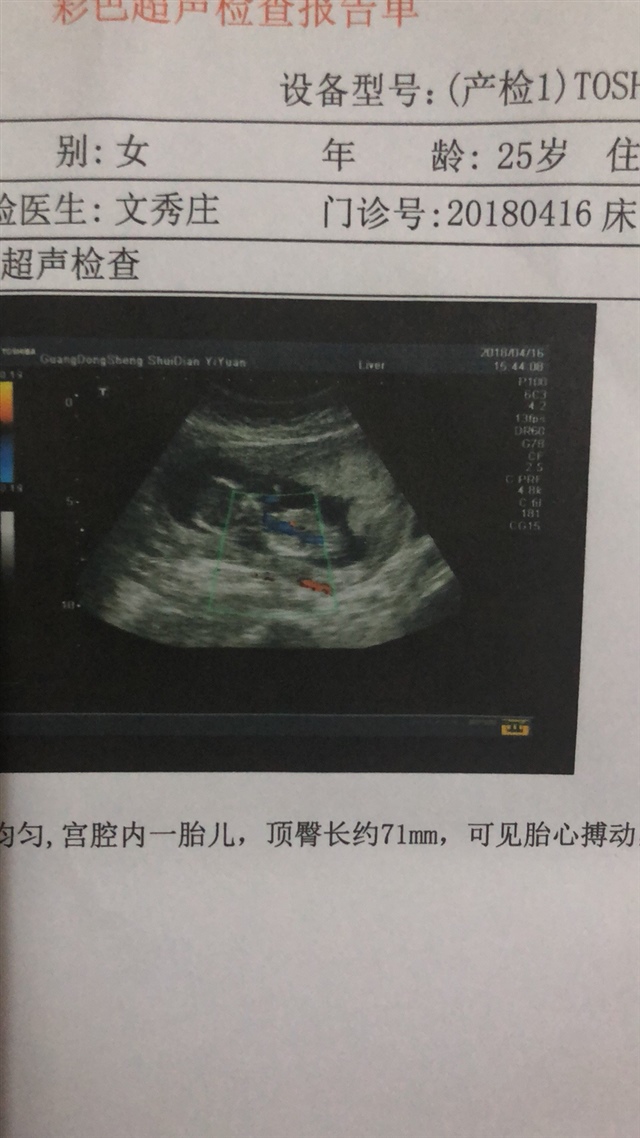

孕13周+1天